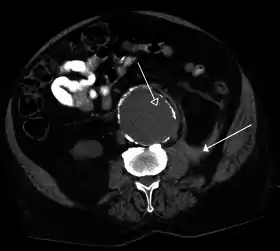

![]() صورة بالأشعة المقطعية تظهر تمزق أم الدم الأبهرية البطنية | |

- التصوير بالأشعة المقطعية المبرمج (CT): أو يعرف أيضاً بالتصوير بالأشعة المقطعية المحوري المبرمج (CAT)وهو تصوير حلزوني ينتج صوراً ثنائية البعد لكل مقطع رقيق في الجسم. تستخدم الأشعة السينية، ولا ينصح بتكرار هذا التصوير بشكل كبير وذلك لتفادي الآثار الصحية.